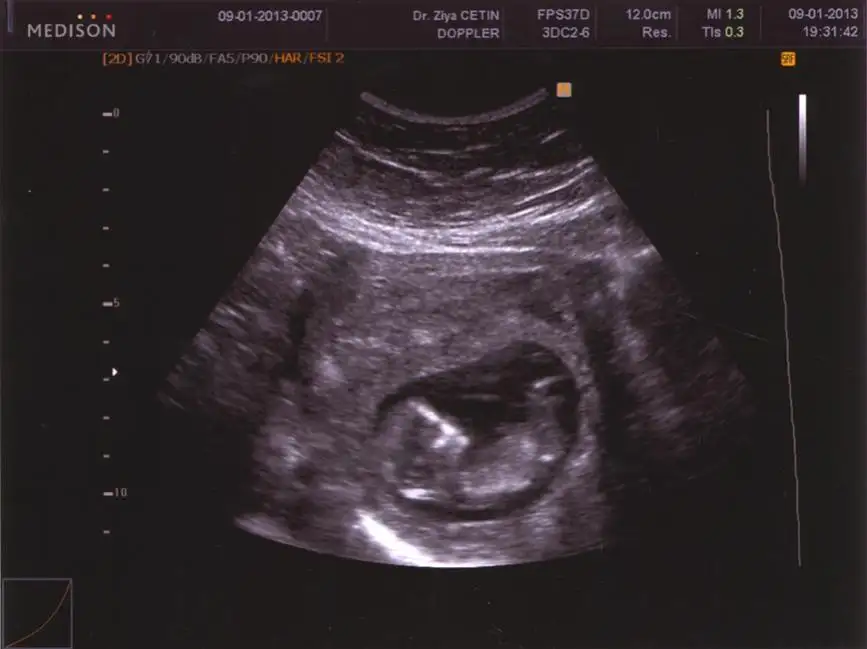

$310120131507.webp hadi kızlarr bizede yorum yapın ;) merakla bekliyorum... 12+0 burda. ultrasonda 12+k çıkmıştı ;)

buda ablamın bebişi. teyzelik görevi olarak bende onun için birşeyler yapayım dedim. resim belki yetersiz gelebilir ama sizce cinsiyeti nedir?